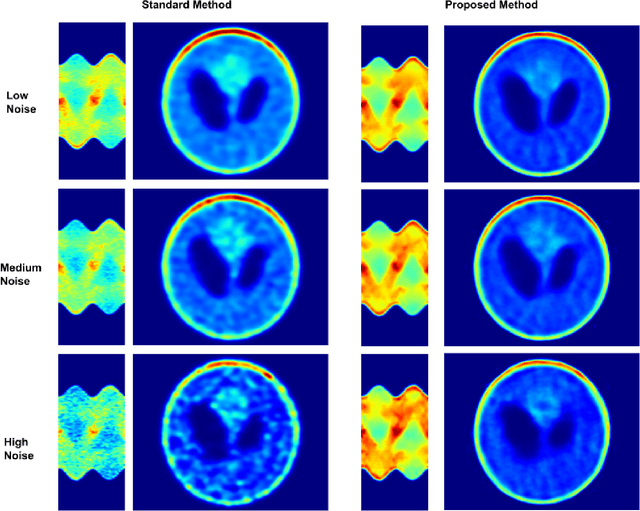

Abstract:A novel method for sinogram denoise based on Generative Adversarial Networks (GANs) in the field of SPECT imaging is presented. Projection data from software phantoms were used to train the proposed model. For evaluation of the efficacy of the method Shepp Logan based phantom, with various noise levels added where used. The resulting denoised sinograms are reconstructed using Ordered Subset Expectation Maximization (OSEM) and compared to the reconstructions of the original noised sinograms. As the results show, the proposed method significantly denoise the sinograms and significantly improves the reconstructions. Finally, to demonstrate the efficacy and capability of the proposed method results from real-world DAT-SPECT sinograms are presented.

Abstract:A novel method for SPECT angle interpolation based on deep learning methodologies is presented. Projection data from software phantoms were used to train the proposed model. For evaluation of the efficacy of the method, phantoms based on Shepp Logan, with various noise levels added were used, and the resulting interpolated sinograms are reconstructed using Ordered Subset Expectation Maximization (OSEM) and compared to the reconstructions of the original sinograms. The proposed method can quadruple the projections, and denoise the original sinogram, in the same process. As the results show, the proposed model significantly improves the reconstruction accuracy. Finally, to demonstrate the efficacy and capability of the proposed method results from real-world DAT-SPECT sinograms are presented.